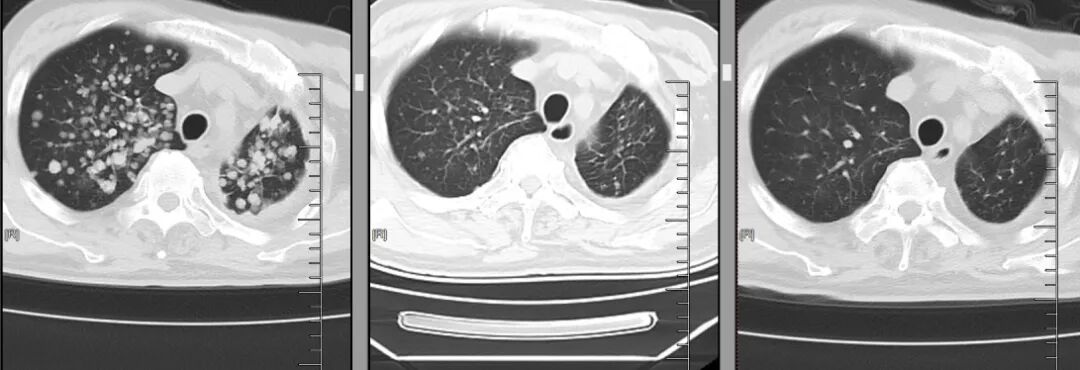

在第二周期治疗前的复查中,当肿瘤科将最新的胸部CT和头颅MRI图像调出来时,结果让人振奋:双肺原本密密麻麻的粟粒样转移结节,大多缩小至模糊不清,肺部原发灶也小了很多;双侧胸膜增厚明显变薄,原本被肿瘤侵犯的纵隔淋巴结也显著缩小;最令人惊喜的是头颅MRI,之前的十余处脑转移灶消失,近乎达到了肿瘤治疗中极具含金量的完全缓解(CR)标准!

△从左至右,肺部肿瘤逐渐减少